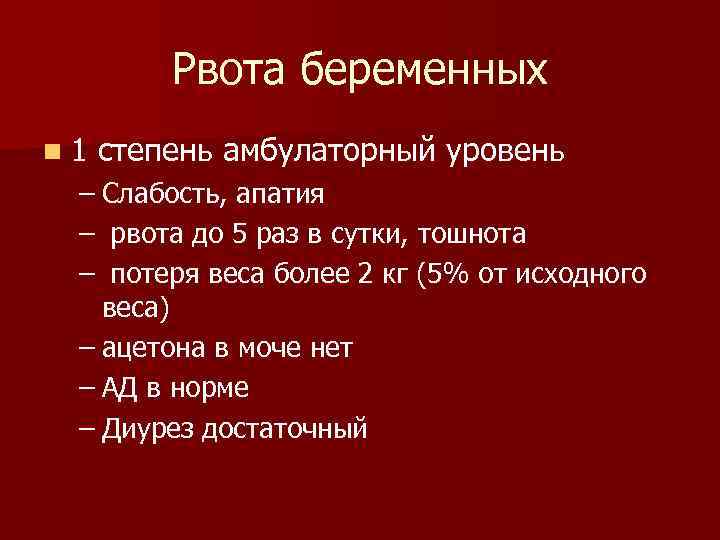

Рвота беременных n 1 степень амбулаторный уровень – Слабость, апатия – рвота до 5 раз в сутки, тошнота – потеря веса более 2 кг (5% от исходного веса) – ацетона в моче нет – АД в норме – Диурез достаточный

Рвота беременных n 1 степень амбулаторный уровень – Слабость, апатия – рвота до 5 раз в сутки, тошнота – потеря веса более 2 кг (5% от исходного веса) – ацетона в моче нет – АД в норме – Диурез достаточный